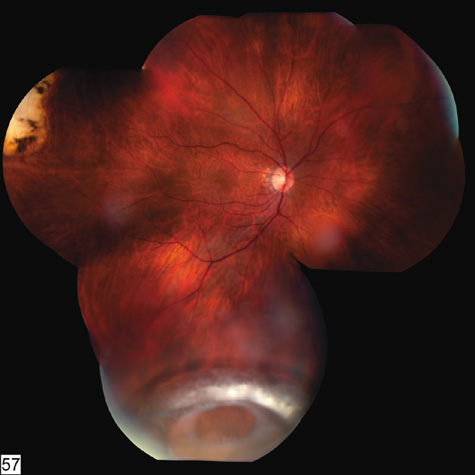

Commotio retinae (Latin, meaning retinal contusion) is a contrecoup injury. It can occur peripherally (Fig. 8) or centrally, in which case it is called Berlin's edema (Fig. 9). Immediately and for several hours after the trauma, the retina appears normal, although the patient may complain of decreased vision. Thereafter, the outer layers of affected retina become opaque. On fluorescein angiography, the opaque retina blocks background choroidal fluorescence, and in most cases there is no leakage into or under the retina (Fig. 10). For years, clinicians had difficulty explaining this blockage, because leakage is expected in conditions with edema. It was then shown in experimental animals and in human autopsy eyes that Berlin's edema is not true edema. The retinal opaqueness is the result of intracellular edema and fragmentation of the photoreceptor outer segments and intracellular edema of the underlying pigment epithelium. There is little or no intercellular fluid.66–69

Fig. 8. Peripheral commotio retinae. The retinal blood vessels are clearly seen because the retinal whitening is in the outer retinal layers.

Fig. 9. Commotio retinae in the macula (Berlin's edema). The visual acuity was 20/25 at the time of the photograph and later improved to 20/15.

Fig. 10. A: Commotio retinae in the macula. B: On the angiogram there is no leakage in the area of commotio retinae.

The visual acuity in commotio retinae varies from 20/20 to 20/400 and does not always correlate with the degree of retinal opacification. There is no known treatment. The prognosis is usually excellent except in cases with associated subfoveolar choroidal rupture and in cases with choroidal rupture with subfoveolar hemorrhage. Poor visual recovery can also be expected in cases with severe retinal pigment epithelial damage. Serous retinal detachment (Fig. 11) signals this condition, which can be confirmed by leakage of fluorescein into the subretinal space.70

Fig. 11. A: Serous detachment of the macula and intraretinal and vitreous hemorrhage after the eye was struck with a baseball. B: Three months later. The hemorrhages have cleared, revealing severe pigment epithelial necrosis. The visual acuity is counting fingers.

The late manifestations of contrecoup injury to the retinal pigment epithelium (RPE) vary from minor atrophic changes that are seen as transmission defects on fluorescein angiography to massive hyperplasia and migration of the RPE. This later condition results in bone corpuscular and granular pigmentation that resembles retinitis pigmentosa (Fig. 12).71,72 The traumatic pigmentary changes may be confined to the posterior pole, to the periphery, or to certain quadrants, or they may be more widespread. When the trauma to the RPE destroys photoreceptor cells, localized visual field defects result. Arcuate field defects are not found because the overlying nerve fiber nearly always remains intact.